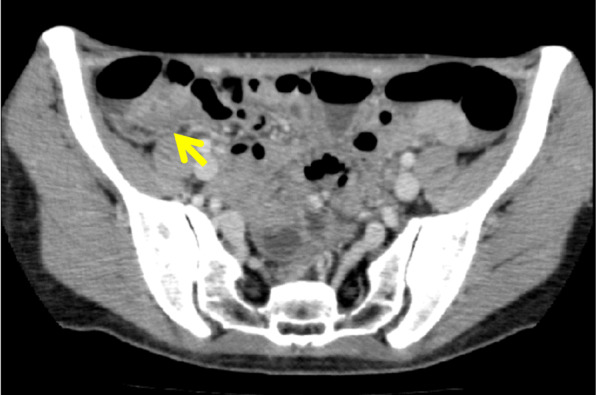

On abdominal CT, an intensely stained mass with a 30-mm diameter, including a low-density region, was observed in the cecum. No lymph node swelling was noted around either the cecum or ileocolic artery (Fig. 1).

Fig. 1.

On abdominal CT, an intensely stained mass with a 30-mm diameter, including a low-density region (arrow), was observed in the cecum